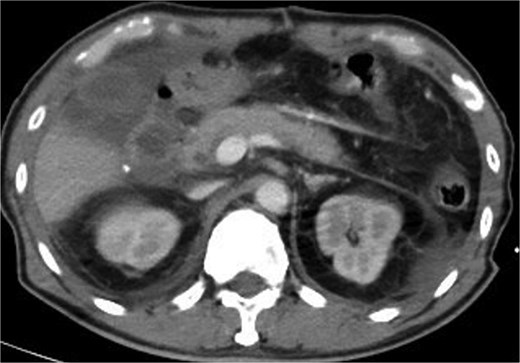

After stabilization in the surgical intensive care unit, a contrast-enhanced whole-body computed tomography (CT) scan (Fig. 3) on postoperative day 2 revealed no active bleeding or pancreatic parenchymal/ductal injury. On postoperative day 5, the patient underwent staged reconstruction. Intraoperative findings demonstrated extensive bile leakage from the anterior wall of the second portion of the duodenum, consistent with advanced erosion and friable tissue, which precluded the feasibility of a Roux-en-Y duodenojejunostomy. Reconstruction consisted of gastrojejunostomy and pyloroplasty, colonic anastomosis, and feeding jejunostomy. Postoperative care included total parenteral nutrition with gradual advancement to jejunostomy feeding. The patient subsequently developed a delayed liver laceration with intra-abdominal hematoma, traumatic pancreatitis, gastrojejunostomy leakage, and colonic anastomotic leak, all of which were managed conservatively. Nevertheless, the course was complicated by duodenal stump leakage with a high-output biliary fistula refractory to standard management, with drainage volumes reaching ~1000 ml/day.

CT scan showed no active bleeding or pancreatic parenchymal/ductal injury.